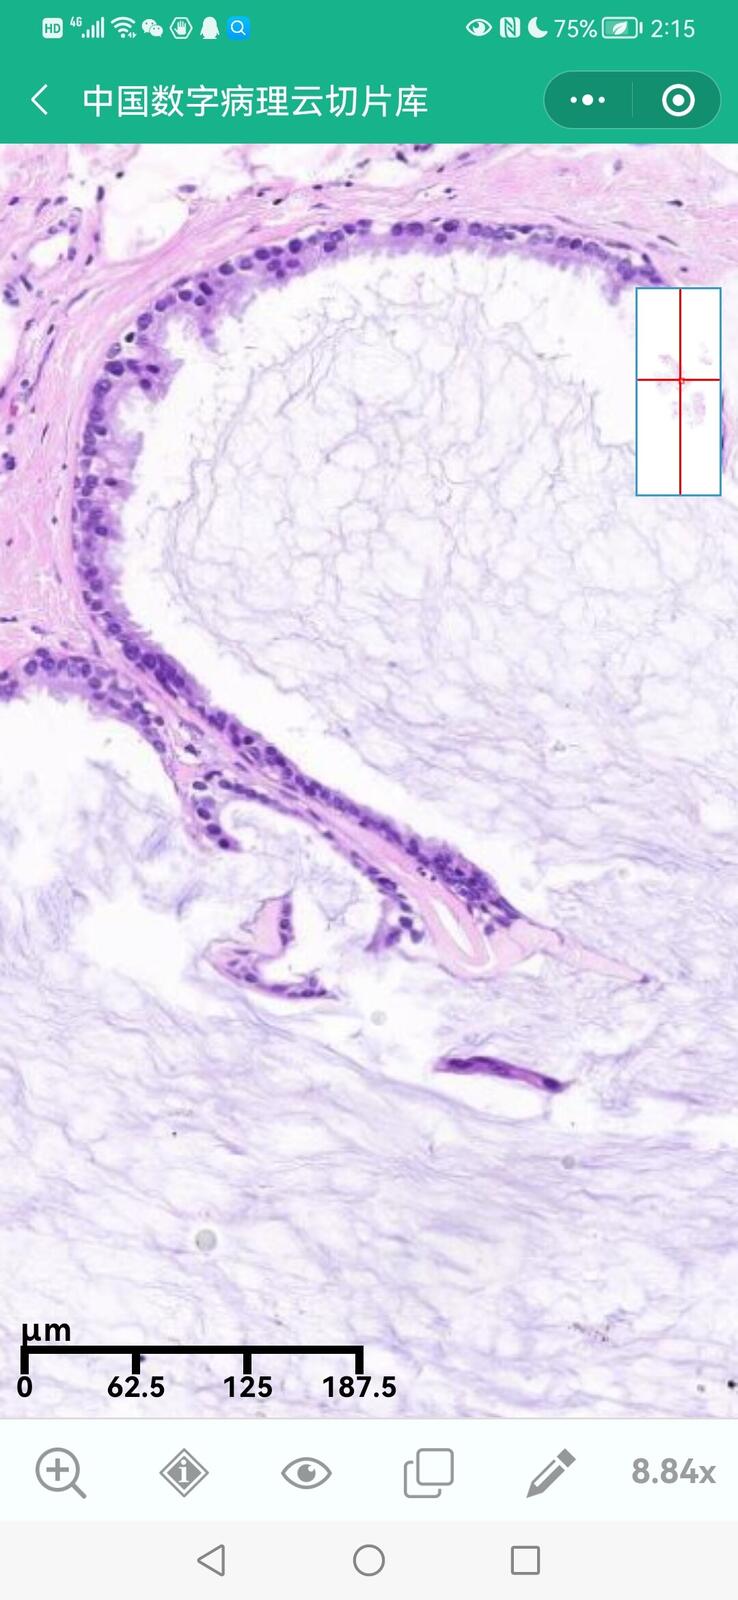

史炯

主任医师

南京鼓楼医院

病理科